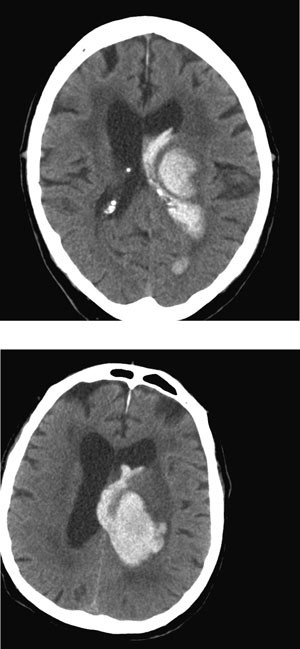

Tidligere trodde man at intracerebral blødning var en øyeblikksbegivenhet der blødningen fant sted i løpet av minutter og nesten umiddelbart stoppet grunnet koagulasjon og mottrykk fra omgivende hjernevev. Vi vet nå at bortimot 40 % av hematomene der den første CT-undersøkelsen utføres innen tre timer etter symptomdebut ekspanderer i løpet av de første timene (17) (fig 2). Antakelig skyldes dette en kombinasjon av fortsatt blødning fra det rumperte kar og mekanisk skade av omgivende kar, noe som fører til blødninger også fra disse (20). CT-angiografi viser at kontrast akkumuleres ekstravasalt i hematomet hos nesten halvparten av dem som undersøkes innen seks timer etter symptomdebut. Slik lekkasje er assosiert med økt vekst av hematomet og økt dødelighet (21). Erkjennelsen av at blødningen ofte fortsetter i flere timer etter debuten kan ha stor betydning for moderne behandling av hjerneblødning.

Intracerebral blødning er en alvorlig tilstand – 35 – 50 % av pasientene dør i løpet av den første måneden, halvparten av disse i løpet av de første to døgn (24). Etter et halvt år er bare ca. 20 % blitt så bra at de er uavhengige av hjelp fra andre (24). De viktigste prediktive faktorer for tidlig død er redusert bevissthetsnivå og stort volum på blødningen. I en pasientserie døde over 90 % av dem med Glasgow Coma Scale (GCS) < 9 og blødningsvolum > 60 ml innen en måned, mot 17 % av dem med GCS > 8 og < 30 ml blod (25). Blødningens volum kan estimeres ved formelen A x B x C dividert med 2, der A er blødningens største diameter, B er diameteren vinkelrett på A og C er antall snitt med synlig blod multiplisert med snittykkelse (25).

Nytten av kirurgisk evakuering av supratentorielle hematomer er omstridt. Randomiserte studier med kraniotomi versus beste medisinske behandling har ikke vist gevinst av kirurgisk intervensjon (33). I ikke-randomiserte pasientserier er det som regel heller ikke vist nytte av kirurgi. Stuporøse eller komatøse pasienter kan i enkelte situasjoner opereres på vital indikasjon, selv om hovedregelen er at man avstår fra kirurgi ved alvorlig bevissthetsreduksjon – GCS < 5. Små hematomer (< 10 ml) eller hematomer med minimale nevrologiske utfall ekspekteres. Tidlig kirurgisk evakuering av hematom, innen fire timer etter debut, kan innebære økt dødelighet grunnet tidlig reblødning (34). Kirurgisk evakuering anbefales derimot ved cerebellar blødning, grunnet faren for trykk mot vitale strukturer i hjernestammen, noe som kan ha fatale konsekvenser (fig 3), ved blødning med assosiert arteriovenøs malformasjon eller aneurisme, som bør behandles for å forebygge nye blødninger, og kanskje hos unge pasienter med moderat eller stor lobær blødning og tegn til klinisk forverring (19).